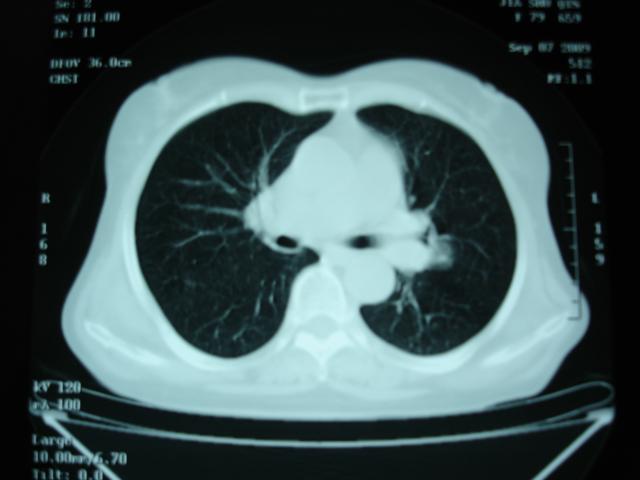

以下是引用卜一在2009-9-7 19:51:00的发言:[br][br] 1 左侧胸内甲状腺占位-多考虑甲状腺腺瘤! 2、左肺门占位-建议增强扫描以便明确性质。 3 慢支并感染! [br]

以下是引用shibing在2009-9-7 20:40:00的发言:[br]左侧胸内甲状腺占位-多考虑甲状腺腺瘤! 2、左肺门占位-建议增强扫描以便明确性质。 3 慢支并感染! [br]